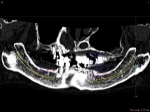

ショートインプラント

術前術前骨の高さが不足している場合、通常のインプラントでは処置が不可能なものが多い。特殊なショートインプラントを用いて可能になる例。 術前 術前CT像術前CT像術前CT像、下歯槽神経が下あごの中央部を走行しているため利用できる骨の高さが少ない。 埋入予定計画埋入予定計画埋入予定計画 術後レントゲン術後レントゲン、ひだりは少し神経をおそれすぎてやや埋入深度が不足、しかしこれでもしっかりと骨と固着した。

上部装着後のレントゲン像上部装着後のレントゲン像上部装着後のレントゲン像 術前口腔内写真術前口腔内写真術前口腔内写真 術後口腔内写真術後口腔内写真術後口腔内写真、食事がおいしくなったと非常に満足されている。